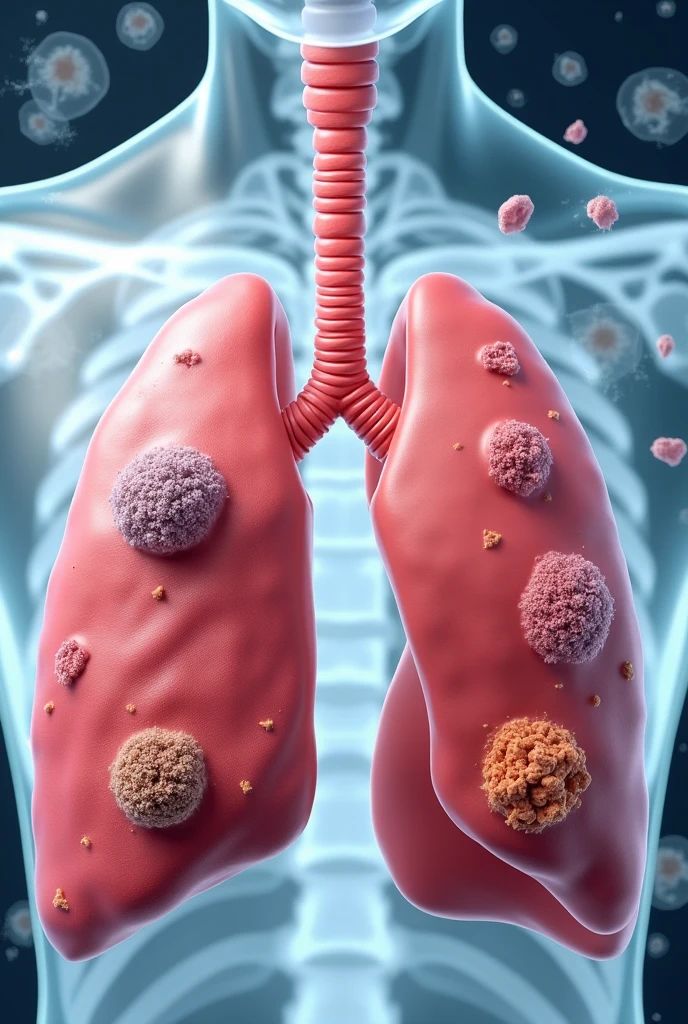

Lung cancer is a disease that originates in the lungs and is characterized by the uncontrolled growth of abnormal cells. These cells can multiply rapidly, invade surrounding tissues, and spread to other parts of the body through the bloodstream or lymphatic system. While smoking is the leading risk factor, lung cancer can also occur in non-smokers due to exposure to secondhand smoke, air pollution, genetic predisposition, and harmful substances in certain work environments.

Lung cancer is primarily classified into two main types: non-small cell lung cancer (NSCLC) and small cell lung cancer (SCLC). NSCLC is the most common form, accounting for about 85% of cases, and includes subtypes such as adenocarcinoma, squamous cell carcinoma, and large cell carcinoma. On the other hand, SCLC is less common but tends to grow and spread more aggressively. Since each type responds differently to treatment, early detection and a tailored treatment approach are crucial for improving outcomes.

Lung Cancer Staging

Lung cancer is categorized into stages based on how extensively it has spread. The stages range from Stage 0, where the cancer is limited to a small, localized region, to Stage IV, where it has metastasized to distant parts of the body. Determining the stage is essential, as it plays a key role in choosing the most appropriate treatment plan and in estimating the patient’s prognosis.

Stage IV is the most advanced stage, where the cancer has spread to distant parts of the body.